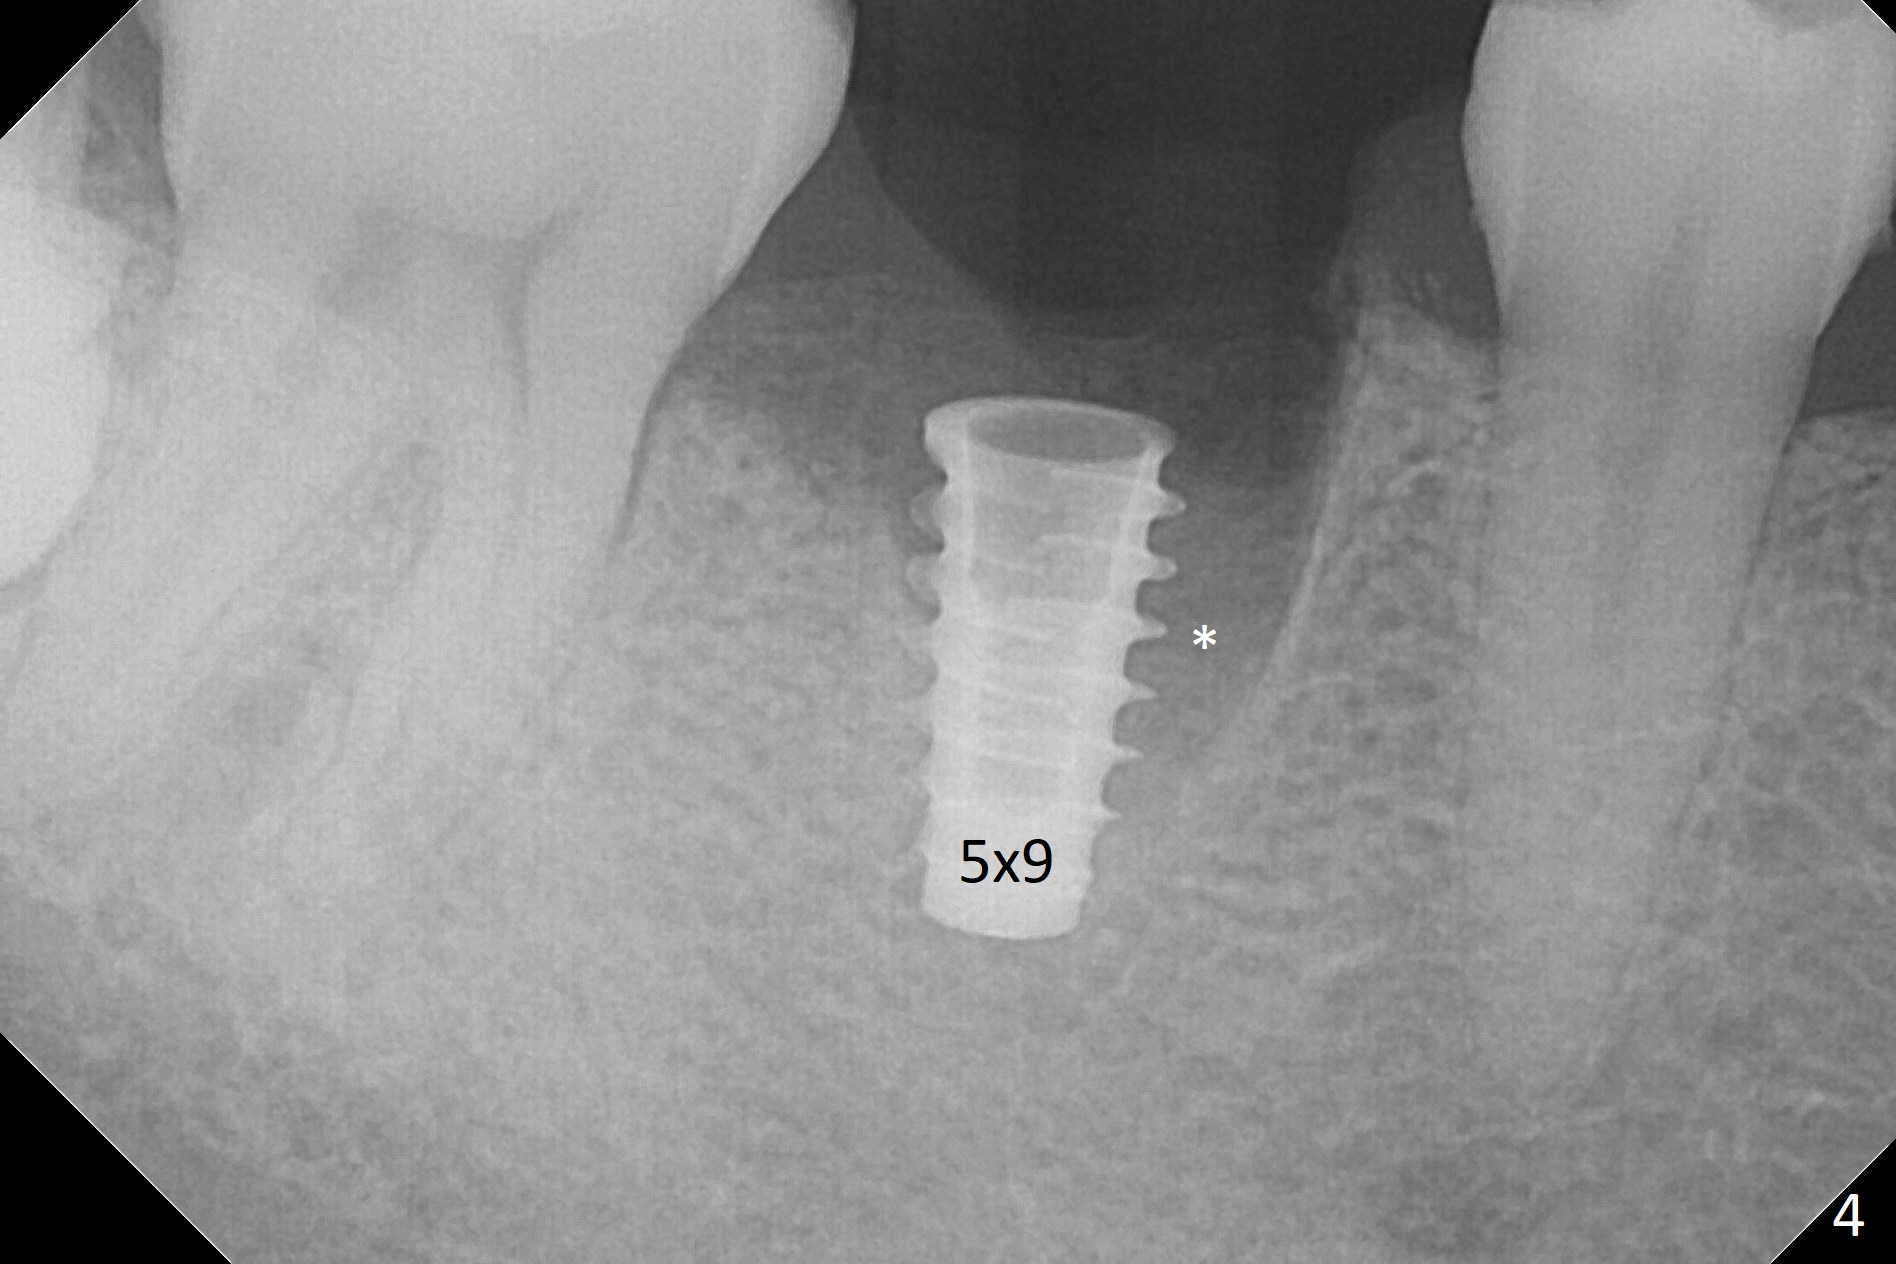

After removal of the residual roots at #30 (Fig.1), a thin septum (Fig.2 *) is removed with Rongeur (Fig.3). Following use of 4.8 mm Magic Drill, a 5x9 mm dummy implant is placed (Fig.4). To reduce socket gap (*), a 6 mm IBS implant is inserted with >50 Ncm (Fig.5). What is unexpected is heavy reduction in the height of a 6.5x4(3) mm abutment (A) because of the short crown height of the lower posterior teeth (Fig.1) and supraeruption of the tooth #3. The immediate provisional is unstable postop. The remade one dislodges soon, so does the abutment (Fig.6, 3 months postop). It appears that bone pattern in the distal socket changes.